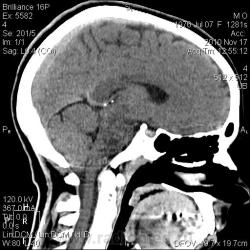

Тип патологии:

Область исследования:

Методы исследования:

- https://radiomed.ru/sites/default/files/styles/case_slider_image/public/user/2841/arnolda-kiari_1_st0004.jpg?itok=ZfK-mqct